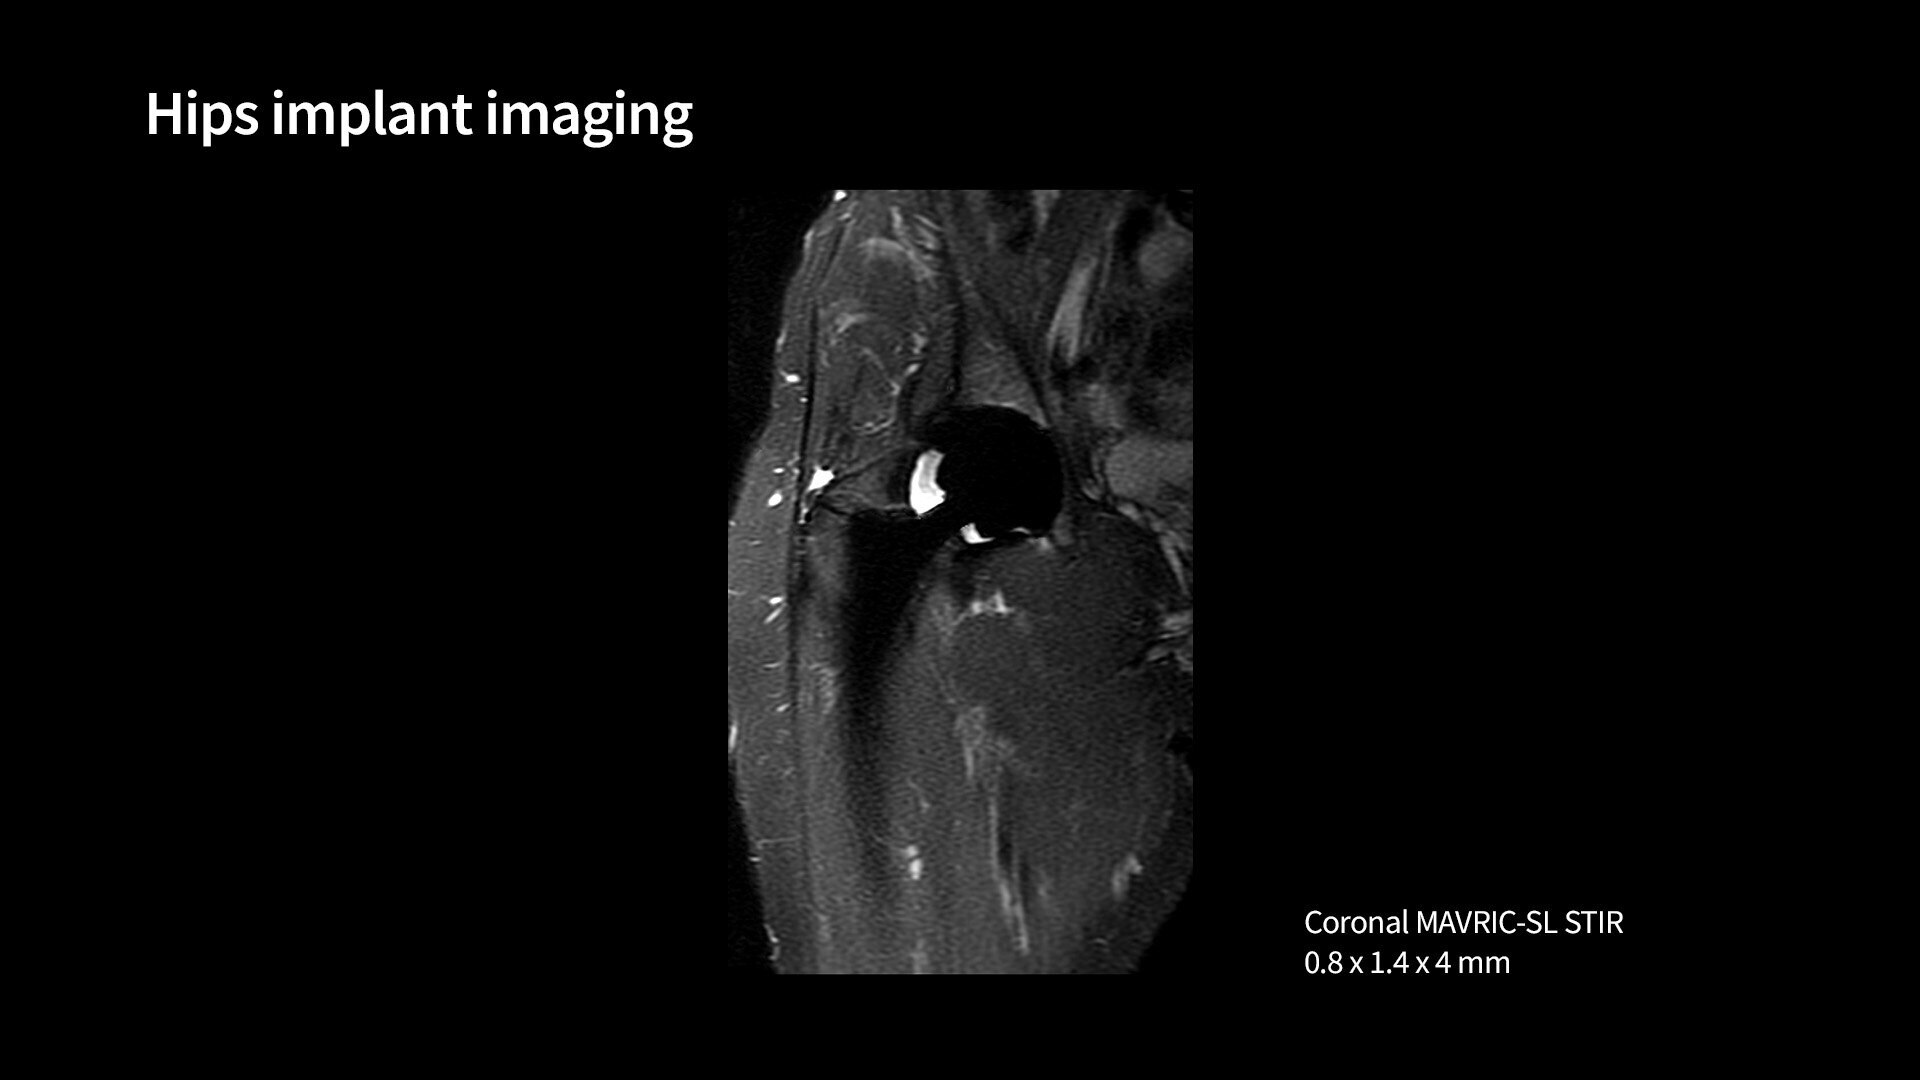

<p>MAVRIC SL &amp; HyperMAVRIC</p>